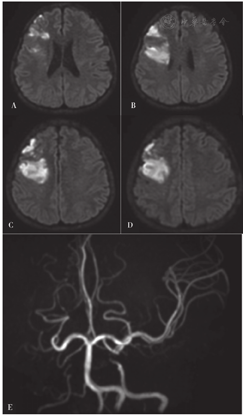

2019-01-02,患者因"右侧肢体无力2 d"而又一次入住滨州医学院附属医院(距离上次住院时间为1年2个月)。患者入院前2 d无明显诱因出现右侧肢体无力,上肢不能抬起及持物,下肢行走拖曳,为求系统诊疗而就诊于滨州医学院附属医院,门诊以"脑梗死"收入院。查体:血压为133/74 mm Hg,心率为127次/min,意识清,言语流利,伸舌偏右,右侧上肢肌力为0级、肌张力减低,右侧下肢肌力为3级、肌张力正常,双侧腱反射(+++),右侧指鼻试验及跟膝胫试验不合作,双侧Babinski征(+),双侧Chaddock征(+),下腹部可见一长约12 cm的剖宫产手术瘢痕、无渗血、渗液、切口愈合可,NIHSS评分为7分。颅脑MRI检查结果:左侧额叶、左侧顶叶急性脑梗死灶;双侧额叶、右侧放射冠软化灶;头颈部MRA检查结果:双侧颈内动脉及右侧大脑前动脉、右侧大脑中动脉未见显影(见图3),考虑闭塞、烟雾病?建议行头颈部CTA或DSA。颈动脉、椎动脉及双侧锁骨下动脉超声检查结果:右侧颈动脉内中膜不均匀增厚;左侧颈内动脉中远端闭塞或极重度狭窄;右侧颈内动脉起始段以远闭塞或极重度狭窄;双侧颈外动脉、双侧椎动脉、双侧锁骨下动脉均呈明显低阻力频谱。TCD检查结果:双侧颈内动脉严重狭窄或闭塞不除外(右侧为著,右侧眼动脉侧支循环开放);左侧大脑中动脉近端或颈内动脉末端及大脑前动脉狭窄;左侧大脑后动脉狭窄或代偿性改变;右侧椎动脉狭窄不除外;可能符合烟雾病TCD改变。甲状腺彩超检查结果:甲状腺弥漫性病变,血流丰富,流速增高。脑DSA检查结果:左侧颈内动脉近端萎缩变细,远端止于眼动脉,显影延迟;右侧颈内动脉发出1 cm后闭塞;左侧后交通动脉开放,供血左侧颈内动脉末端及左侧大脑中动脉、大脑前动脉,显影略延迟;右侧大脑后动脉发出分支,供血右侧大脑中动脉区(见图4)。心电图检查结果:窦性心动过速。甲状腺功能指标:游离三碘甲状腺原氨酸为10.28 pmol/L,游离甲状腺素为28 pmol/L,促甲状腺激素<0.005 mU/L,抗甲状腺球蛋白抗体为146.4 U/ml,甲状腺过氧化物酶抗体为56.7 U/ml。

注:A~D为颅脑DWI,示左侧额叶、顶叶片状高信号影(考虑为脑梗死);E~G为颅脑MRI,示双侧额叶、右侧放射冠软化灶;H~I为头颈部MRA,示双侧颈内动脉及右侧大脑前动脉、右侧大脑中动脉未见显影,左侧后交通动脉开放